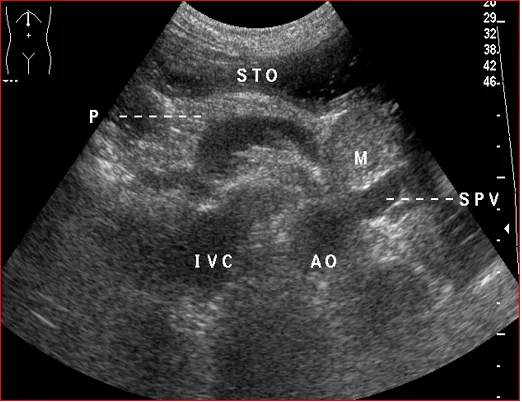

●经胰体矢状切面

标志为:腹主动脉长轴。

应显示:胰体短轴、腹主动脉、肠系膜上动脉。

胰体-纵切扫查